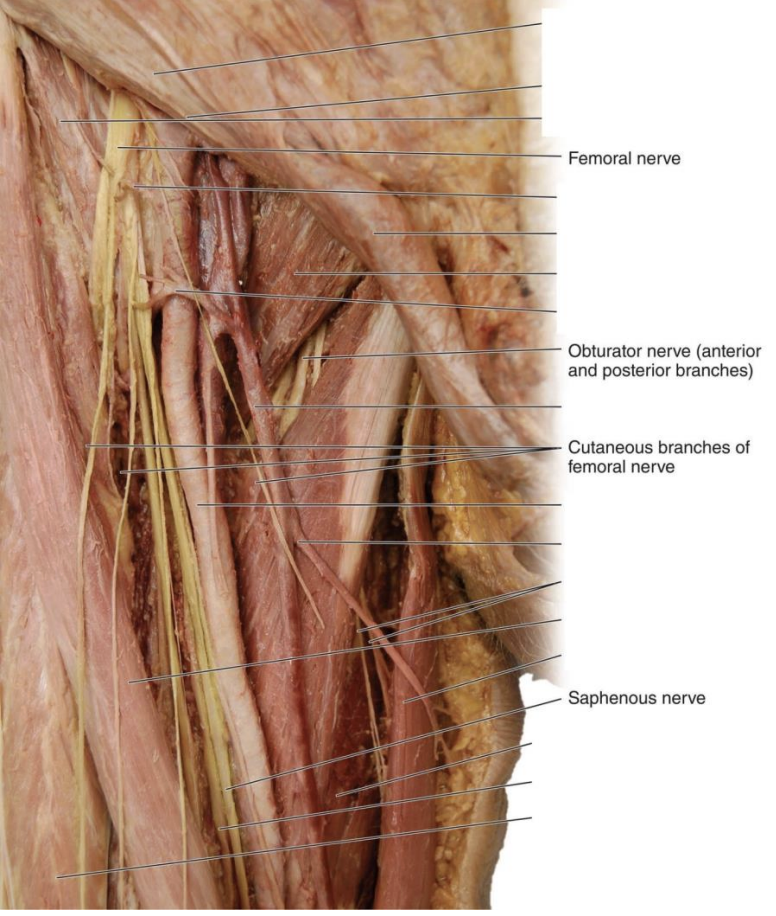

Femoral Nerve

L2-3